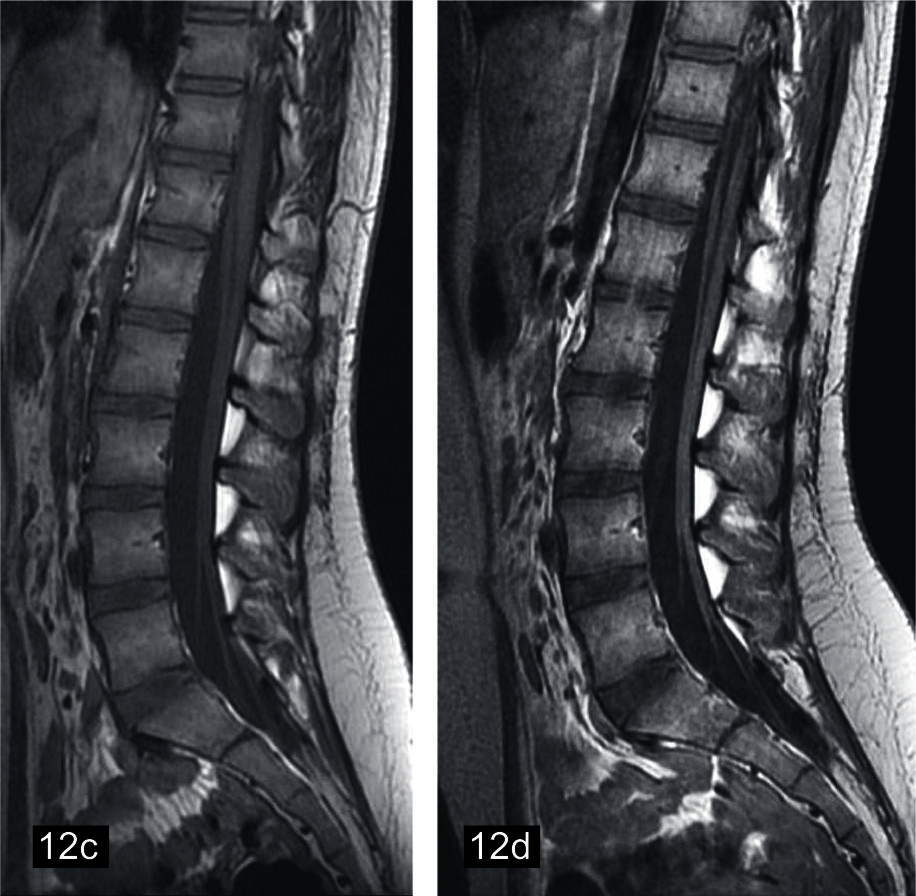

Figura 12

Sindrome de Guillain Barré en niño de 9 años

(a) Secuencia neurográfica IDEAL water en ponderación T2, que muestra engrosamiento e hiperseñal difusa de los ramos del plexo lumbar. Imagenes convencionales de columna en FSE ponderación T1 (b) axial con contraste, (c) sagital sin contraste, (d) sagittal con contraste, se observa engrosamiento y realce de raices de cauda equina.